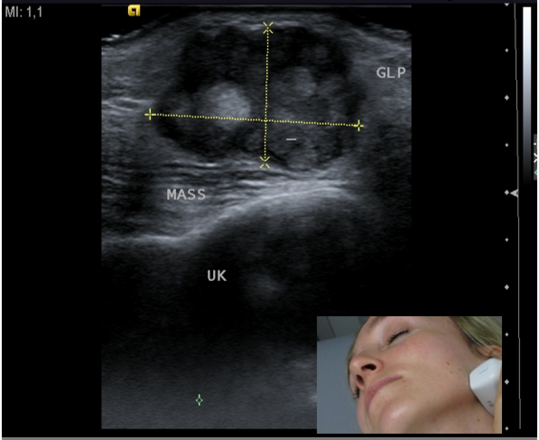

Die Sonografie dient der Ausdehnungsbestimmung (Staging) von tumorösen Veränderungen der Kopf-Hals-Region. Vor- und nach Behandlungen werden besonders die Halslymphknoten untersucht, ob sich tumorverdächtige bildmorphologische Veränderungen zeigen.